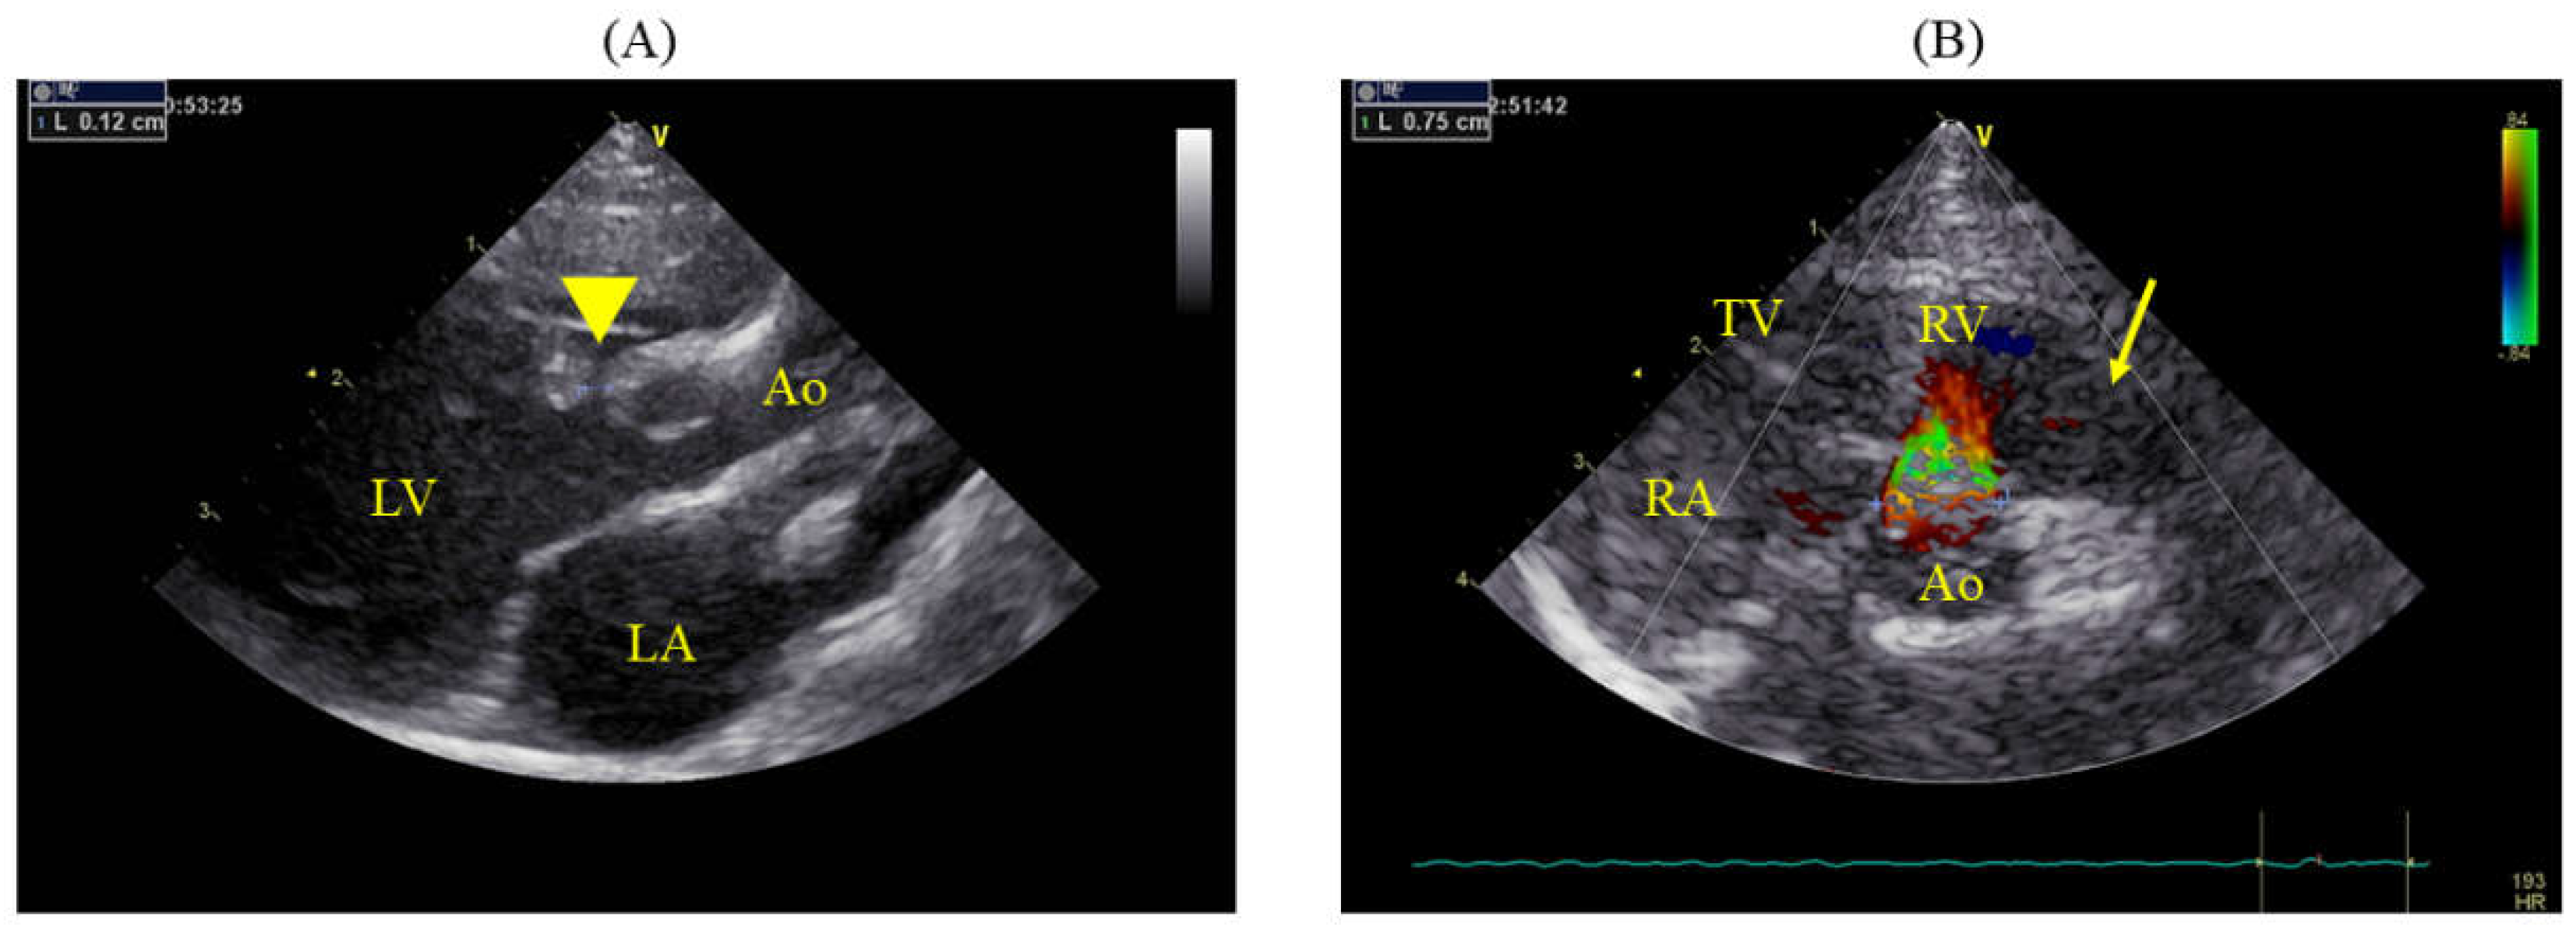

Significant enlargement of the pulmonary artery was evident (main pulmonary artery-to-aorta diameter ratio 1.29 (11.0/8.5 mm); normal value in dogs < 1.0 [12] (Figure 2). Although no tricuspid or pulmonary valve regurgitation and no evident signs of pulmonary hypertension (PH) were noted [12,13], the pulmonary to systemic blood flow ratio calculated by using Doppler was 2.96. Given the enlargement of the left side of the heart, surgical intervention was deemed necessary, and the cat underwent surgical correction under cardiopulmonary bypass. Pre-anesthesia included subcutaneous administration of atropine (0.025 mg/kg; Atropine Sulfate; NIPRO ES PHARMA Co., Ltd., Osaka, Japan), followed by intravenous administration of cefazolin (20 mg/kg, with additional doses every 2 h during surgery; Cefazolin Sodium for Injection, Nichi-Iko Pharmaceutical Co., Ltd., Toyama, Japan ), and slow intravenous injection of dexamethasone (0.2 mg/kg; dexamethasone injection A; Nippon Zenyaku Kogyo Co., Ltd., Fukushima, Japan). The cat was oxygenated with 100% oxygen for 5 min and received an intravenous injection of fentanyl (2 μg/kg; Fentanyl injection 0.5 mg; Janssen Pharmaceutical K.K., Tokyo, Japan). Subsequently, alfaxalone (5 mg/kg; Alfaxan multidose; Meiji Animal Health Co., Ltd., Kumamoto, Japan) was administered intravenously, and anesthesia was maintained with isoflurane (1–2%; Isoflurane; Mylan Pharma Co., Ltd., Osaka, Japan). During surgery, a continuous rate infusion (CRI) of fentanyl (5 μg/kg/h) was administered for pain management. Rocuronium bromide (0.3 mg/kg; Eslax intravenous; MSD K.K., Tokyo, Japan) was administered intravenously to halt respiration, with additional doses of 0.1 mg/kg administered every 40 min as needed. If the blood pressure dropped during surgery, isoflurane was discontinued, and anesthesia was maintained with a CRI of alfaxalone (5–8 mg/kg/h).

Figure 2. Right parasternal short-axis view at the level of the aortic valve showing significant dilation of the MPA. The diameter of the aorta is 8.5 mm, and that of MPA is 11.0 mm, indicating an MPA:Ao ratio of 1.29. Ao: aorta; MPA: main pulmonary artery; RV: right ventricle.